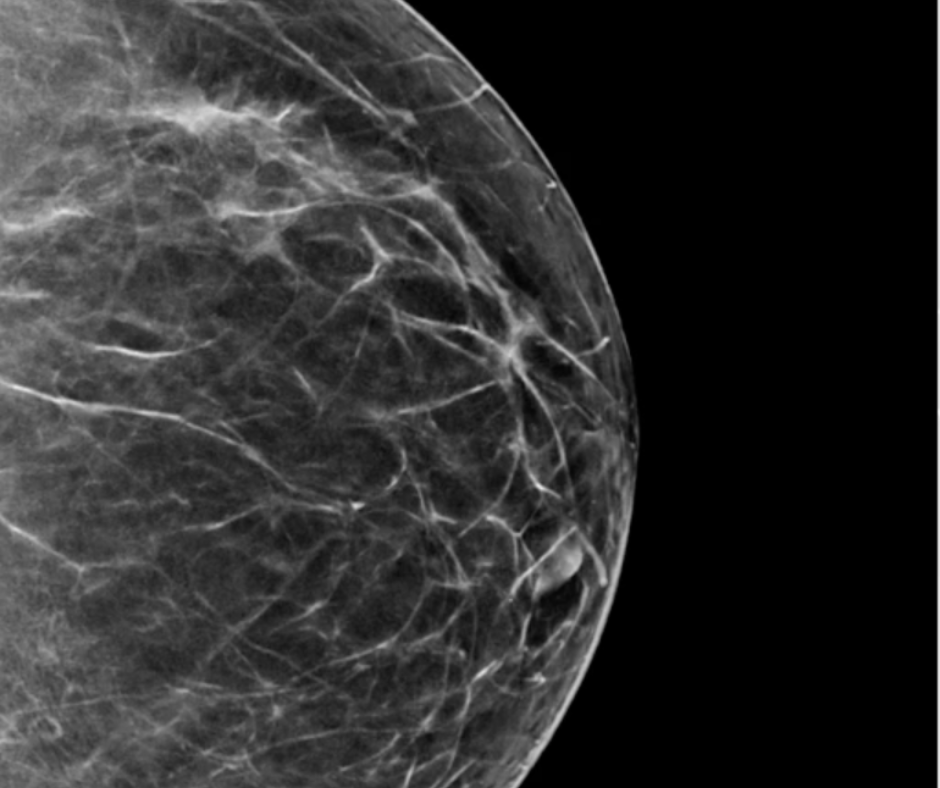

L'IA améliore le taux de détection du cancer pour la mammographie numérique et la tomosynthèse mammaire numérique

L'utilisation de l'intelligence artificielle (IA) d'appoint a doublé la valeur prédictive positive (PPV) des examens de mammographie numérique (DM) dans l'ensemble et a conduit à une précision supérieure à 90 % pour la DM et la tomosynthèse mammaire numérique (DBT) dans la détection du cancer du sein chez les femmes avec un taux élevé risque, selon les résultats de recherche présentés récemment à la conférence du Congrès européen de radiologie (ECR) à Vienne, en Autriche.